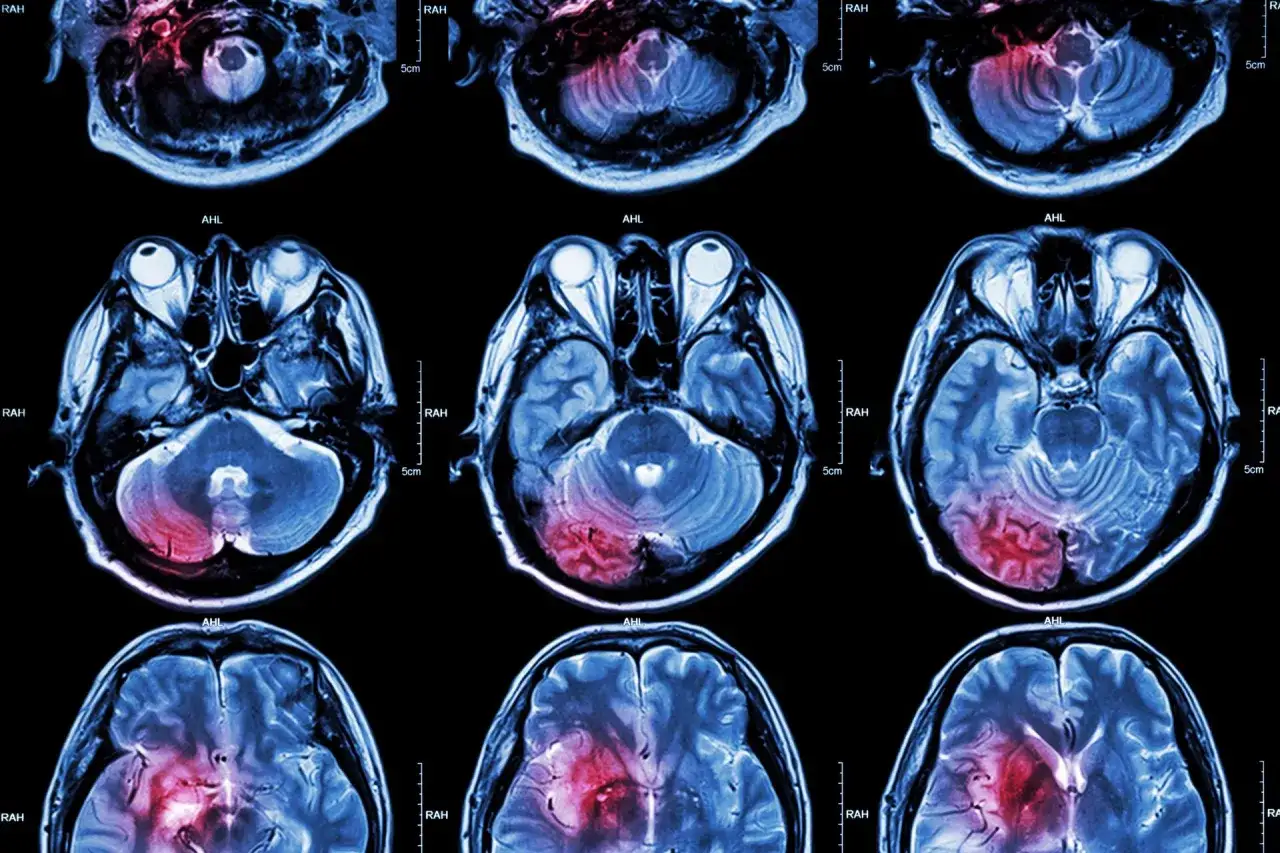

Udar mózgu to nic innego jak nagłe zaburzenie krążenia krwi w mózgu. Wyobraź sobie, że Twój mózg, podobnie jak każdy inny organ, potrzebuje stałego dopływu tlenu i składników odżywczych, które dostarczane są wraz z krwią. Kiedy ten dopływ zostanie przerwany czy to przez zablokowanie naczynia krwionośnego, czy przez jego pęknięcie i wylew krwi komórki nerwowe zaczynają obumierać w ciągu zaledwie kilku minut. To właśnie ta nagłość i szybkość uszkodzeń sprawia, że udar jest stanem bezpośredniego zagrożenia życia i wymaga natychmiastowej reakcji. Szybka pomoc medyczna jest absolutnie kluczowa, aby zminimalizować trwałe konsekwencje.

Udar niedokrwienny, często nazywany zawałem mózgu, jest zdecydowanie najczęstszym typem, odpowiadającym za około 80-87% wszystkich przypadków. Dochodzi do niego, gdy tętnica doprowadzająca krew do określonej części mózgu zostaje zablokowana. Najczęściej przyczyną jest skrzeplina (zakrzep), która tworzy się w naczyniu krwionośnym lub wędruje z innego miejsca w ciele (np. z serca) i zatyka mniejszą tętnicę w mózgu. Inną częstą przyczyną jest blaszka miażdżycowa, która narasta w tętnicach, zwęża je, a następnie może pęknąć, prowadząc do powstania zakrzepu. W rezultacie tej blokady, obszar mózgu pozbawiony tlenu i składników odżywczych zaczyna cierpieć, a jego komórki obumierają.

Udar krwotoczny (wylew): Gdy pęknięte naczynie zalewa mózg

Udar krwotoczny, powszechnie znany jako wylew, jest rzadszy odpowiada za 15-20% udarów ale często ma znacznie cięższy przebieg. W tym przypadku problemem nie jest zablokowanie, lecz pęknięcie naczynia krwionośnego. Krew wylewa się poza naczynie, uciskając tkanki mózgowe i powodując ich uszkodzenie. Może to być krwotok śródmózgowy, gdy naczynie pęka wewnątrz mózgu, lub krwotok podpajęczynówkowy, gdy krew wylewa się na powierzchni mózgu. Chociaż jest rzadszy, udar krwotoczny odpowiada za około 40% zgonów z powodu udaru, co podkreśla jego wysoką śmiertelność i powagę sytuacji.